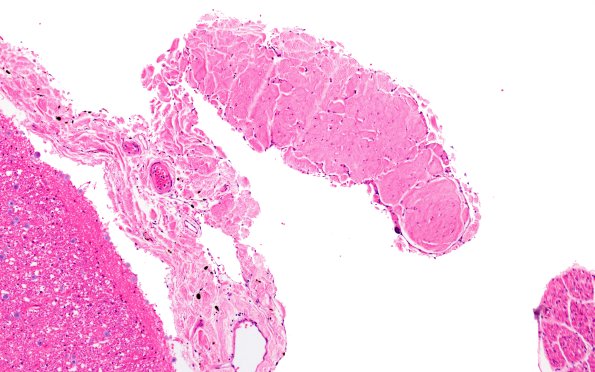

1A3 Denticulate ligament (Case 1) H&E N10 10X

1A3,4 One ligament from image #1A2 at two magnifications demonstrating its fibrous constituents. (H&E)